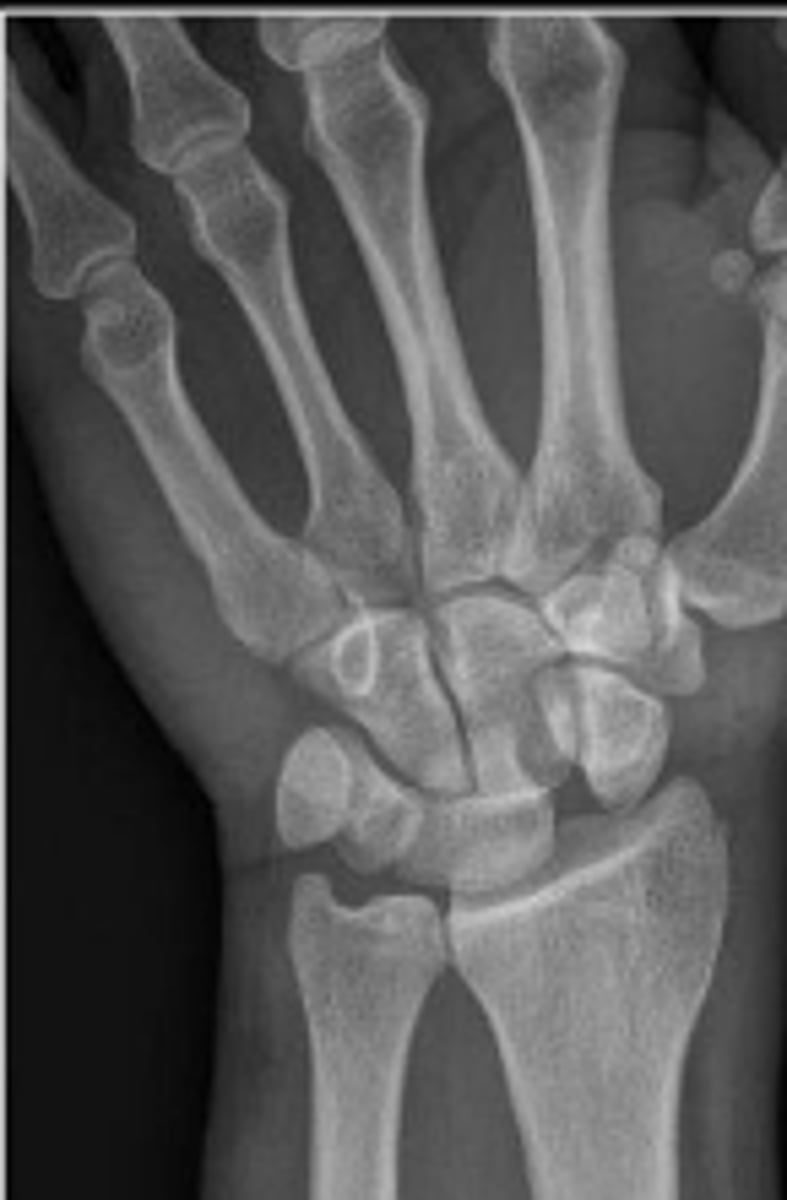

Medial oblique of the left wrist

What is the name of the radiographic view?